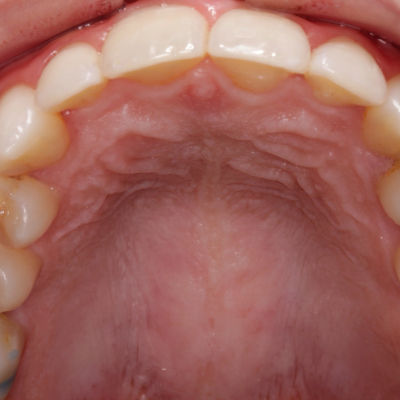

Sabia que ,em muitos casos, a falta de espaço na arcada dentária pode levar à não erupção de peças dentárias?Neste caso, por falta de espaço ,o canino não erupcionou , tendo de ser tracionado para a arcada dentária.

Neste caso, por falta de espaço ,o canino não erupcionou, tendo de ser tracionado para a arcada dentária.